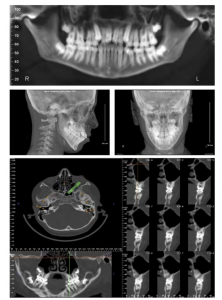

CBCT looks similar to traditional 2D panoramic images, except they allow the dentist to view and manipulate images in 3D. They provide better visualization and location of the hard and soft tissues and obtain crisp, clear, detailed images of your teeth, jaws, nerves, airway, and sinus cavities. These 3D images enhance our treatment and diagnostic capabilities in areas such as: dental implant planning and treatment, wisdom teeth removal, root canal therapy (endodontics), sleep apnea, and Temporal Mandibular Joint Dysfunction (TMJ).